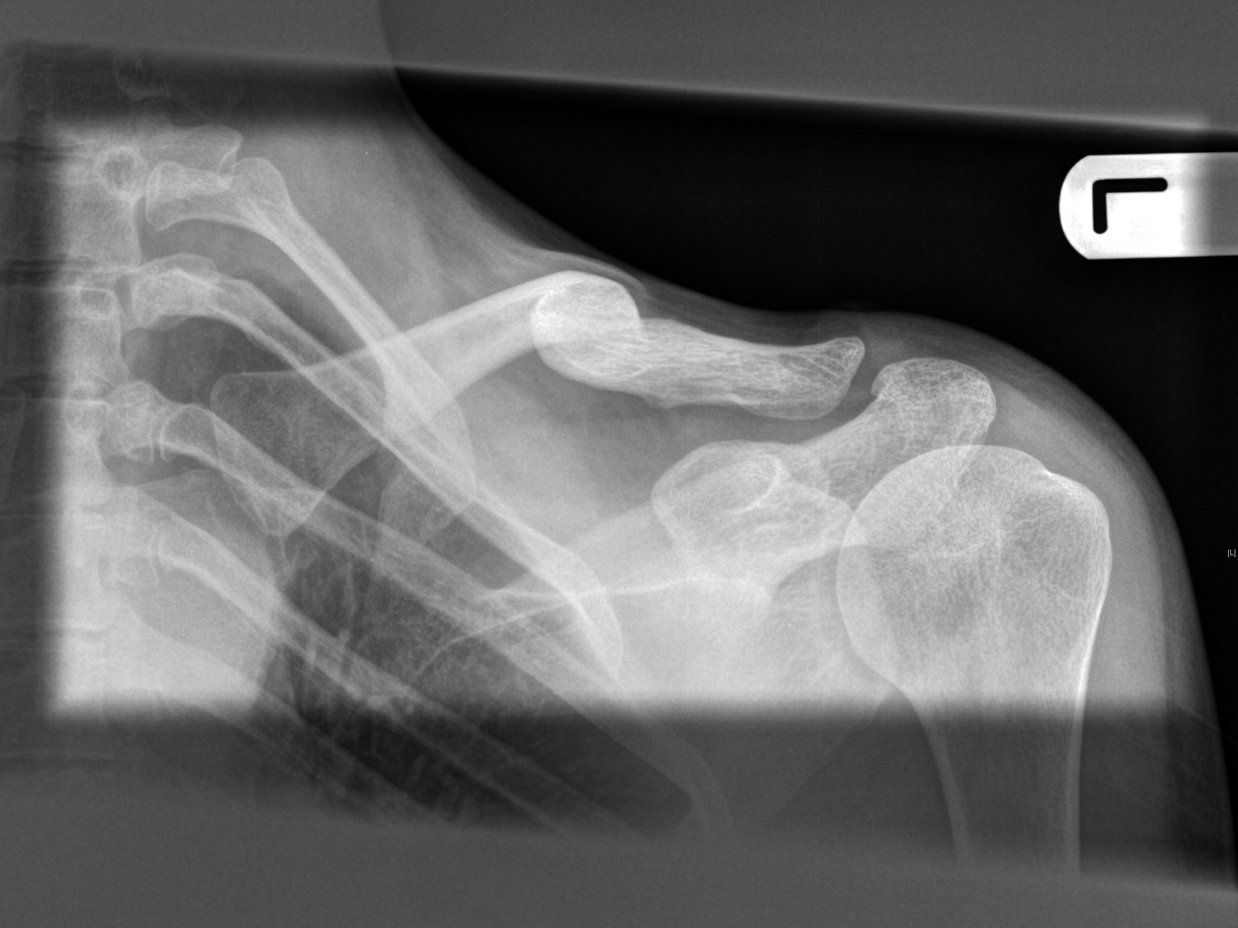

I perceive the feeling of being airborne on a bike and the experience of recovering from injury as complete opposites. It is a move from feeling graceful, strong and able to conquer anything to being clumsy, slow, weak and barely coping with everyday tasks. Once the hospital has immobilised you and the injured area of the body stiffens up then even basic tasks are painfully slow; tying shoe laces, brushing hair, getting dressed. Navigating around public space I am aware of how fragile I am and how vulnerable I am compared to others. I am constantly aware that my body’s function is impaired. In A Leg to stand on Oliver Sacks writes about his experience of breaking his leg and says he felt like an animal with a broken back dragging its hind legs along (1990: 26). I feel disadvantaged in relation to others, upset by the diminished functionality of my body and bored by restrictions on what I can do. Just living basic life, getting up and showering and dressing takes so much more time and I feel how little I am able to achieve. I long for excitement and adrenaline but my body is not capable of doing the things that produce this. The passiveness makes me feel like I am in a room and watching life on a TV set, as if there is a gap between what I see and what is there. It is as if what I see and experience outside of myself is not ‘real’.